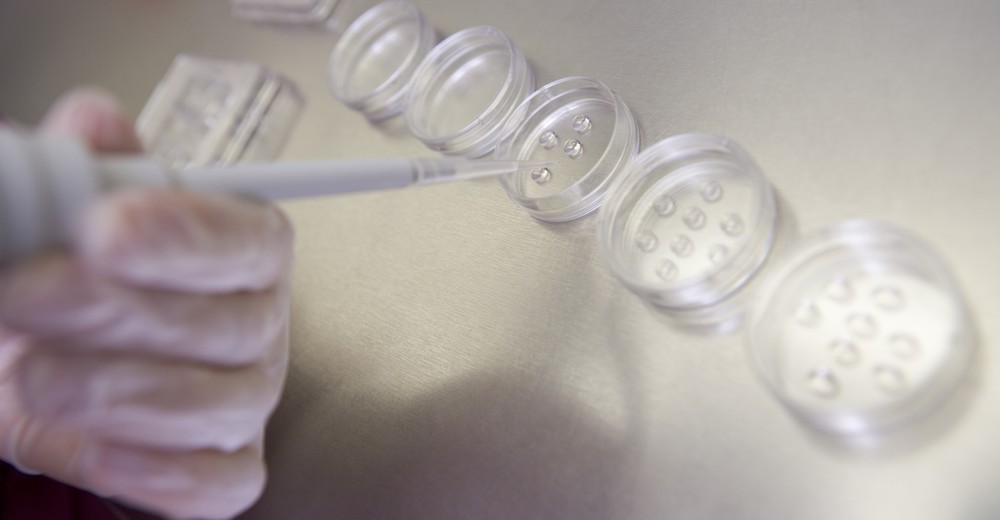

Το μοναδικό ωάριο που λαμβάνεται κατά την ωοληψία, γονιμοποιείται από το σπέρμα του συζύγου και το έμβρυο μεταφέρεται 2-3 ημέρες μετά, πίσω στη μήτρα. Δύο εβδομάδες αργότερα γίνεται το τεστ κυήσεως. Τις δυο αυτές εβδομάδες, επειδή όλα γίνονται με φυσικό τρόπο, δεν χρειάζεται η γυναίκα να λάβει ορμονική υποβοήθηση (προγεστερόνη), εκτός και αν για κάποιο λόγο κριθεί απαραίτητο.